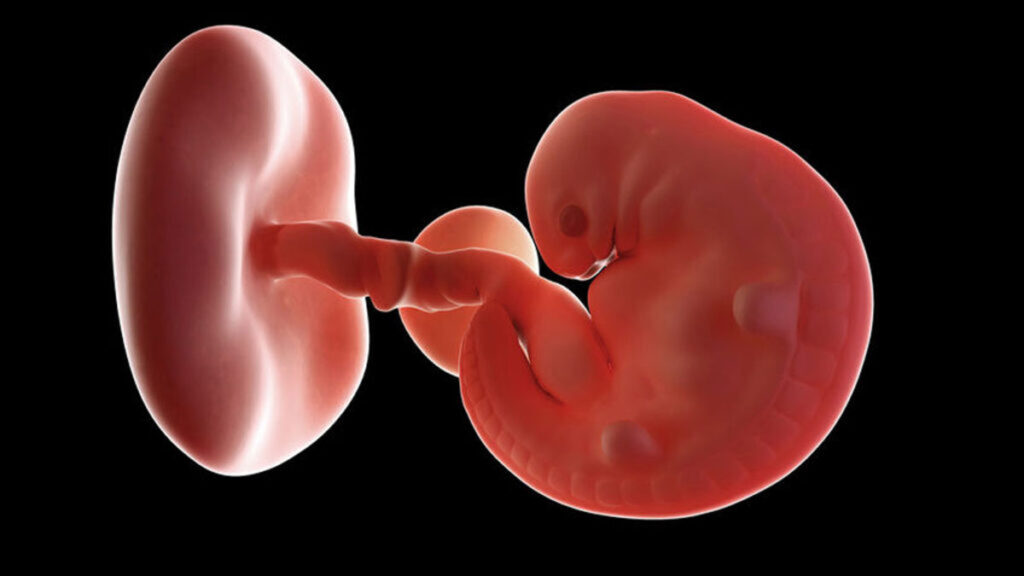

De embryo begint nu vorm te krijgen. Het is nog wel heel ieniemienie maar het hoofdje en het gezicht krijgen al vorm. Je kunt met doppler zelfs het hartje al horen kloppen. Je baby gaat ongeveer 1 mm per dag groeien en dan gaat het best hard. De verhouding gezicht lijfje is nog niet in verhouding maar dat komt allemaal goed. Het hart is in verhouding ook nog erg groot.

Het hoofdje, nek, ogen en oren van je baby zijn inmiddels gevormd. Zijn oogjes staan ver uit elkaar. Zijn mondje wordt gevormd en in allebei de kaken kun je al de knopjes voor de melktandjes terugvinden. De hersentjes zijn ook weer iets verder ontwikkeld en hij heeft nu ook al een bloedsomloop. Ook is er al een begin gemaakt in de ontwikkeling van de organen (nieren, lever en maagdarmsysteem). Deze week begint het hartje van je baby te kloppen! Het klopt erg snel.

Je baby maakt trouwens zelf bloed aan zodat jouw bloedgroep niet hetzelfde hoeft te zijn als die van je kindje. In deze week krijgen alle organen meer vorm. De hersenen en het ruggenmerg zijn ook bijna gegroeid. Kortom er groeit een klein mensje in je.